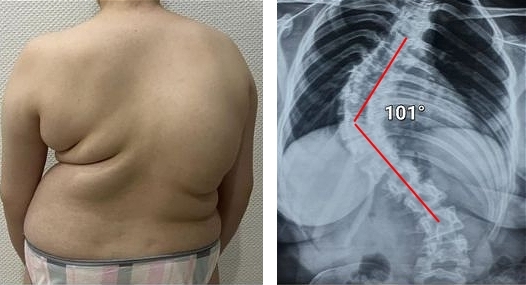

Všechny klouby vyžadují pozornost, ale hlavní je páteř. Postarejte se o ni, dřív než začnou nevratné změny. Podívejte se, co čeká ty, kdo ignorovali signály organismu: KÝLA, POSUN OBRATLŮ, DEFORMACE PÁTEŘE, ZHRBENÍ, ÚPLNÁ ZTRÁTA POHYBU. Nečekejte na okamžik, kdy i jednoduchý pohyb bude mučením!

Podívejte se na tyto fotografie. To se stalo těm, kdo příznaky ignorovali. Dnes jsou bezmocní a mnoho z nich nemá na koho se o péči spolehnout. Opravdu chcete takový osud?

Každý den vás bolesti kloubů přibližují invaliditě! Už tisíce lidí ztratily schopnost pohybu a staly se invalidními. Ničení kloubů a páteře samo nepřejde — jednejte, dokud není pozdě!

— Každý z těchto lidí věřil, že se mu to nestane! Ale výsledek: úplná ztráta pohyblivosti, ochrnutí, amputace — celoživotní závislost na pomoci druhých a INVALIDNÍ VOZÍK! Více než 90 % se stane invalidními jen proto, že včas nepodnikli správné kroky. Stárnutím podmíněné opotřebení kloubů začíná potichu — ignorováním bolesti hážete život do koše!